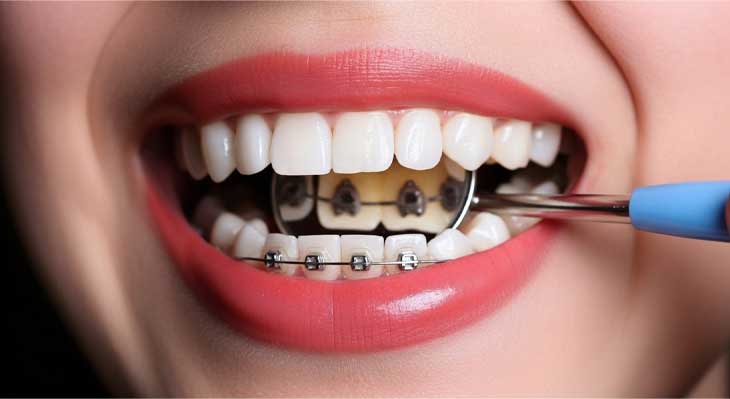

روش های ارتودنسی امروزی بسیار متنوع هستند. بریس های فلزی سنتی به دلیل کارایی بالا همچنان یک گزینه قدرتمند هستند. بریس های سرامیکی ظاهری زیباتر را ارائه می دهند. سیستم های پیشرفته ای مانند دیمون، درمانی راحت تر و سریع تر را نوید می دهند. و در نهایت، ارتودنسی نامرئی با الاینرهای شفاف، یک گزینه فوق العاده برای کسانی است که به دنبال یک درمان کاملا نامحسوس هستند. در موارد خاص، ممکن است نیاز به درمان های ترکیبی مانند ارتوسرجری نیز باشد.

فرآیند اصلاح دندان های نامرتب با ارتودنسی یک مسیر مشخص و برنامه ریزی شده را طی می کند. این فرآیند از چند مرحله کلیدی تشکیل شده است که هر کدام برای موفقیت نهایی درمان ضروری هستند. اولین قدم، یک جلسه مشاوره و معاینه جامع است. در این جلسه، متخصص ارتودنسی با دقت وضعیت دندان ها، فک و صورت شما را ارزیابی می کند. سپس با استفاده از ابزارهای تشخیصی مانند رادیوگرافی و اسکن سه بعدی، یک طرح درمان دقیق و سفارشی برای شما طراحی می نماید. در این مرحله، تمام جزئیات درمان، از جمله طول دوره تقریبی و هزینه ها، برای شما شرح داده می شود.

مرحله بعدی، فاز فعال درمان است. در این مرحله، دستگاه های ارتودنسی (بریس ها یا الاینرها) در دهان شما قرار می گیرند. شما باید به طور منظم (معمولا هر ۴ تا ۸ هفته) برای تنظیم دستگاه ها و پیگیری روند پیشرفت، به کلینیک مراجعه کنید. این دوره که ممکن است از چند ماه تا چند سال طول بکشد، نیازمند همکاری کامل شما در رعایت بهداشت و پیروی از دستورالعمل ها است. مرحله پایانی، پس از رسیدن به نتیجه مطلوب، برداشتن ارتودنسی دندان است. این جلسه با تمیز کردن و پولیش دندان ها همراه است. اما مهمترین بخش، شروع فوری مرحله نگهداری با استفاده از ریتینرها برای تثبیت نتایج و جلوگیری از بازگشت مجدد دندان های نامرتب است.